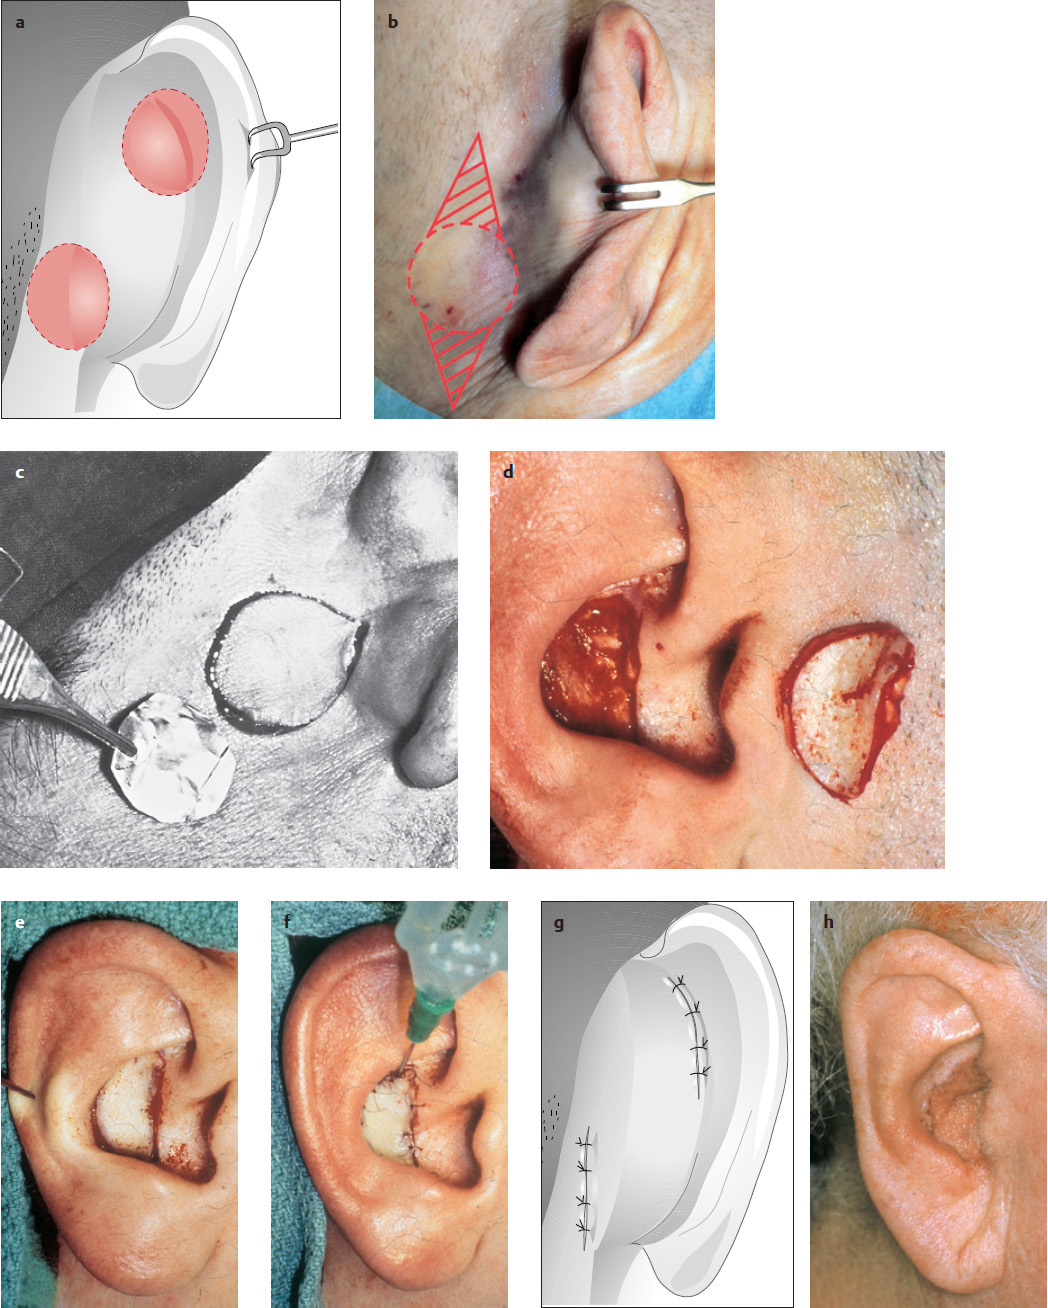

Reconstruction with a Full-thickness Skin Graft

( Fig. 10.3 )

Since large parts of the concha adjoin the mastoid region, full-thickness skin is an option for reconstructing the concha. Reconstruction with a full-thickness skin graft is shown in Fig. 10.3a–h .